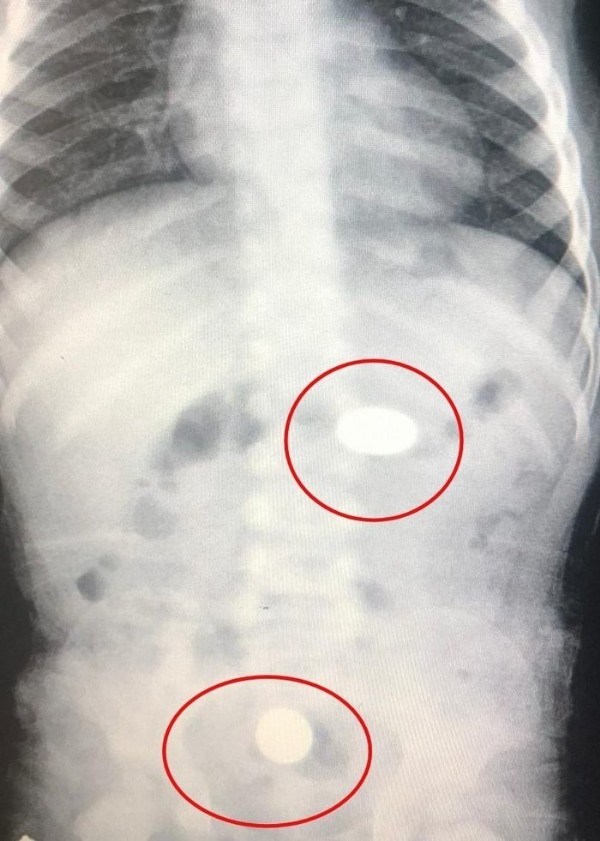

Bursa'nın İnegöl ilçesinde meydana gelen olayda yerde bulduğu 2 adet 50 kuruşu şeker zannedip yutan bebek, hastanede tedavi altına alındı. Yapılan tetkiklerde paralardan birinin bebeğin midesinde, diğerinin ise yemek borusunda kaldığı tespit edildi.

Yapılan tetkiklerde paralardan birinin bebeğin midesinde, diğerinin ise yemek borusunda kaldığı tespit edildi.